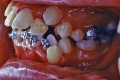

マルチブラケット終了時